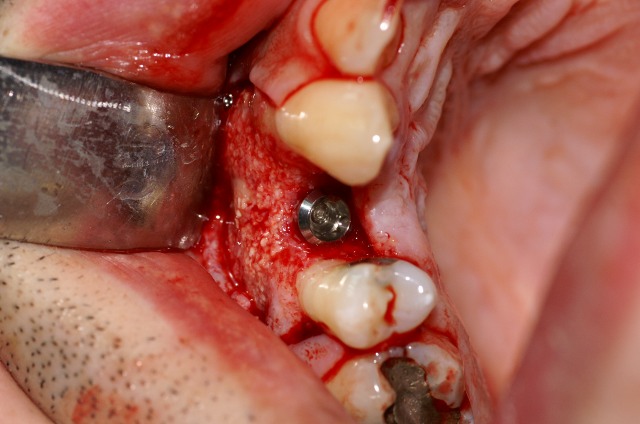

Τοποθέτηση του εμφυτεύματος